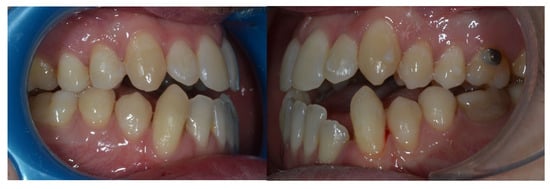

Figure 3. Evolution of treatment after the use of the Carriere appliance with Sagittal First philosophy.

Due to persistent difficulties in extruding the lower left lateral incisor during the initial full set of lower aligners and the lack of response after a second attempt (refinement), a hybrid approach was adopted. A sectional fixed appliance was placed from the lower left canine to the lower right canine using conventional brackets to facilitate the extrusion of the lower left lateral incisor, a movement that had proven ineffective with aligners alone in this case (Figure 4). Concurrently, ¼″, 4 oz Class III elastics were maintained to reinforce sagittal corrections and minimize relapse risk.

Figure 4. Changes in the vertical position of the mandibular incisor (32) achieved through hybrid treatment involving the use of brackets.